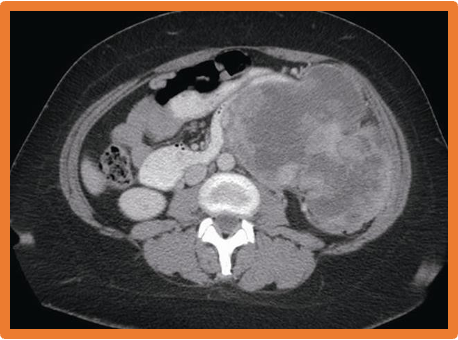

Retroperitoneal Sarcoma-

- CT, MRI